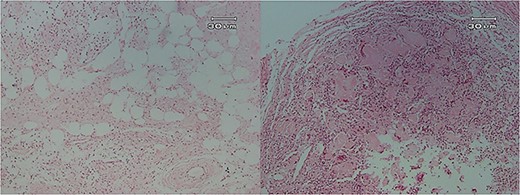

Microscopic examination showed (Figs 4–7) inflamed connective tissue composed of prominent plasma cells mixed with numerous osteoclastic multinucleated giant cells of various sizes with intracytoplasmic asteroid bodies and round Schaumann bodies, which surrounding round to amorphous eosinophilic areas composed of the spindle to stellate cells in fibromyxoid background is also evident.

Histopathologic views of the lesion (H&E staining, ×100 magnification). (A) Inflamed fibromyxoid connective tissue. (B) Area of one granulomatous pattern inflammation with multiple giant cells. (C) Numerous foreign body giant cells admixed with severe chronic.

Histopathologic views of the lesion (H&E staining, ×10 magnification). Inflammation in the connective tissue and foreign body giant cells admixed with severe chronic inflammatory cells.

Histopathologic views of the lesion (H&E staining, ×100 magnification). Inflamed fibromyxoid connective tissue and foreign body giant cells.

Histopathologic views of the lesion (H&E staining×100 magnification) showing chronic inflammatory cells admixed with multinucleated giant cells of varying sizes.